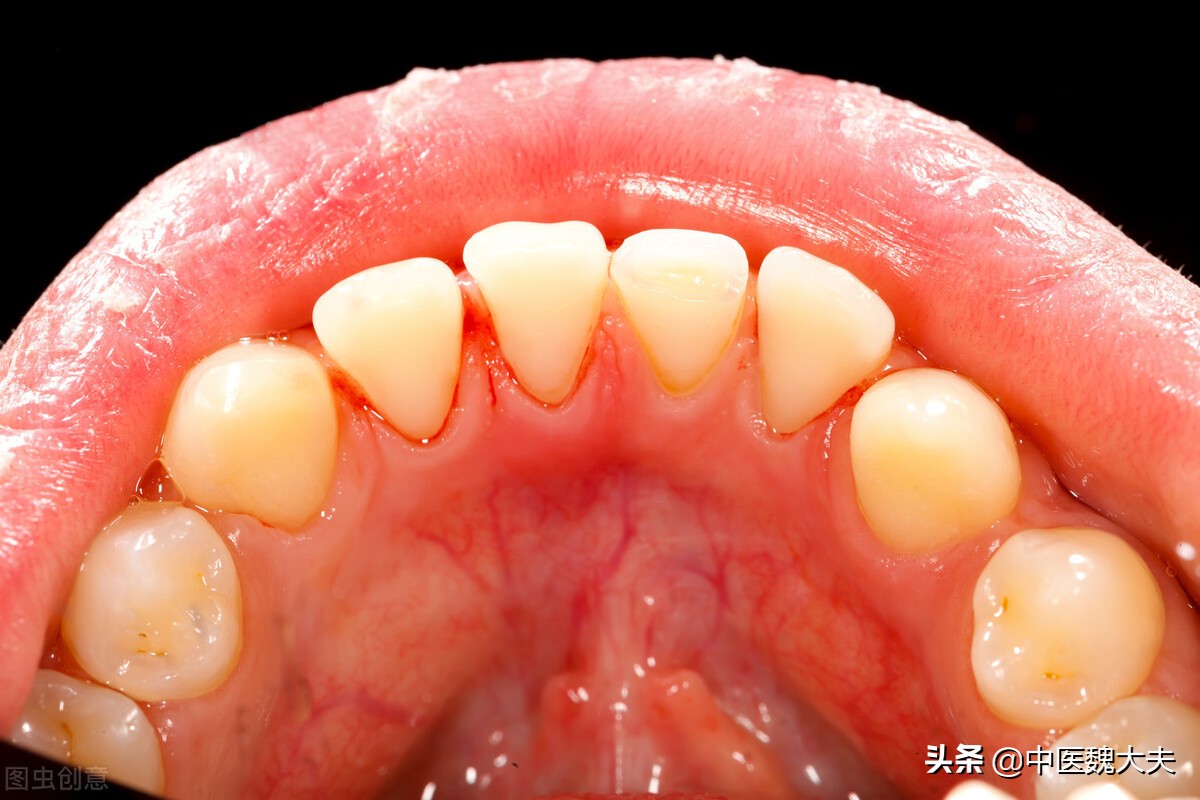

齿衄(牙龈出血):又称牙衄、牙宣,其病变与胃、肾有关。

出血症状:鼻衄,或见吐血,出血势急量多,或见齿龈肿痛出血。